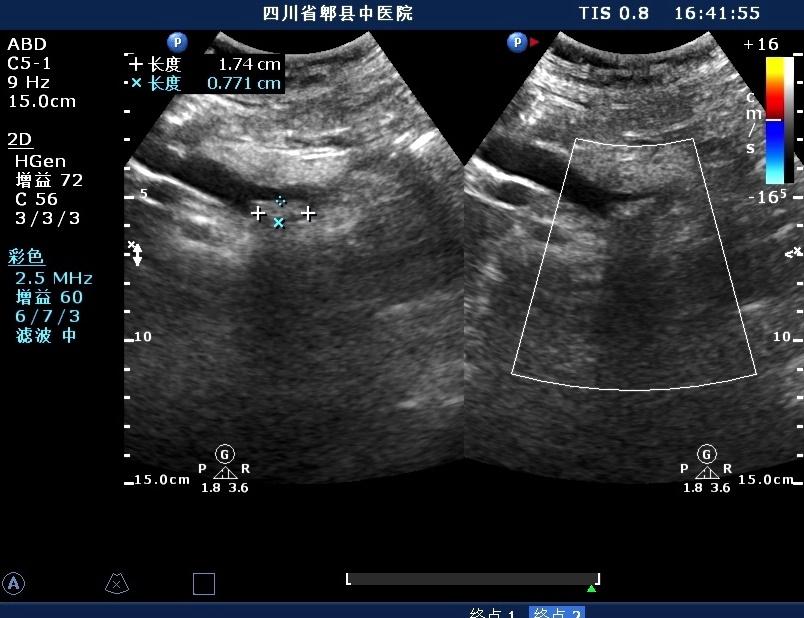

超声如图:胆总管及肝内胆管扩张,呈“平行管征”,胆总管胰腺段可见疏松强回声团堆积,后方可见淡淡声影,左肝外叶胆管内亦可见数个强回声团堆积,后方伴声影。 肝脏及胆总管

左肝内胆管结石